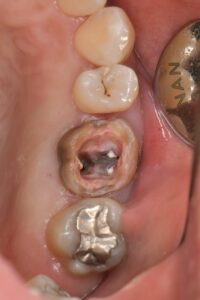

ⅱ.再治療(過去に治療してる根管)の場合

➡過去の充填物やむし歯の除去と隔壁作製、根管内の充填物の除去とクリーニング